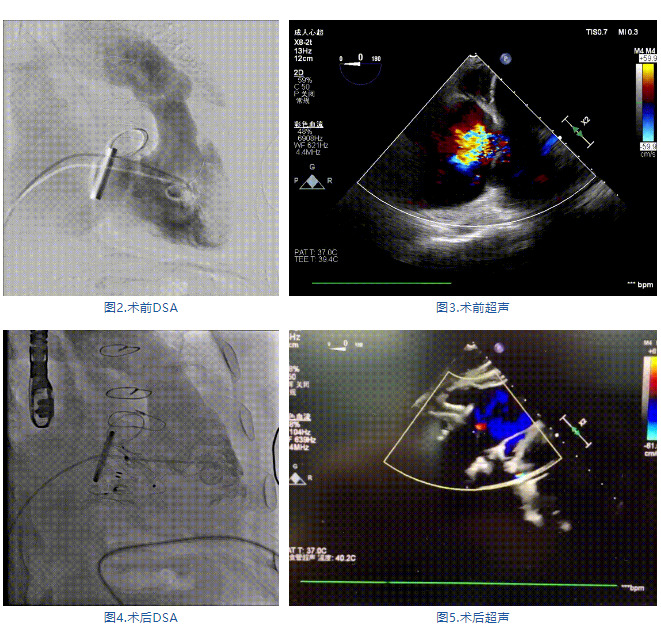

手術(shù)在全麻狀態(tài)下進(jìn)行,郭惠明教授團(tuán)隊采用經(jīng)右側(cè)頸靜脈入路的方式送入輸送器進(jìn)入體內(nèi),并在TEE和DSA的指引下進(jìn)行。在輸送器進(jìn)入右室后釋放室間隔錨定裝置,旋轉(zhuǎn)輸送器,使得錨定裝置對準(zhǔn)室間隔面;而后釋放前瓣夾持件,確定夾持件位于右室側(cè)釋放LuX-Valve Plus人工瓣膜盤片,再使用DSA和超聲確認(rèn)盤片是否位于右房側(cè),同時調(diào)整瓣膜的同軸性。緊接著在DSA和超聲的監(jiān)視下調(diào)整室間隔錨定件貼合室間隔,釋放室間隔錨定裝置。再次確認(rèn)瓣膜的穩(wěn)定性和同軸性后,將輸送器撤出體內(nèi),最終完成LuX-Valve Plus人工瓣膜植入(圖2-5),手術(shù)獲得圓滿成功。患者在手術(shù)室即刻拔除氣管插管,術(shù)后超聲提示LuX-Valve Plus人工三尖瓣瓣膜同軸性良好,瓣架固定牢靠,無反流和瓣周漏。